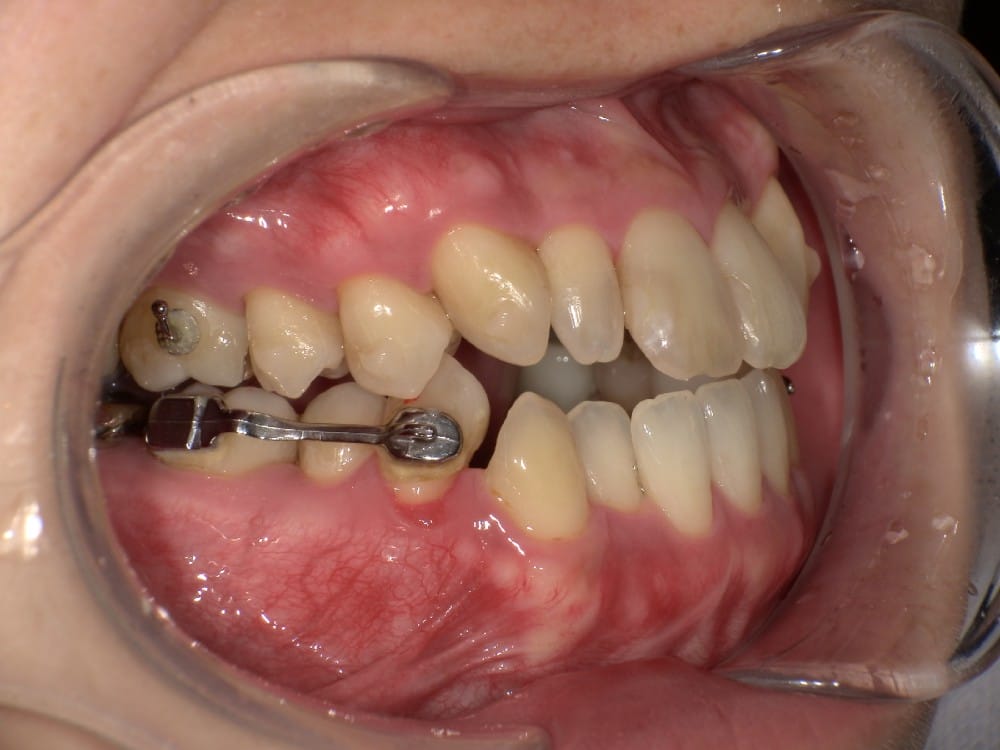

このような奥歯の移動量が大きい症例では、マウスピースだけでは難しいことがあり、カリエールとよばれる装置を補助的に使用し、上下の噛み合わせの前後関係を整えることで、手術を行わずに機能面と見た目の両方が改善することがあります。

一時的に前歯は噛み合わせが開いていますが、受け口の矯正では、最終段階で前歯ばっかりあたって奥歯がしっかり噛まないということも起こりやすいので、あえて狙って動かしています。

今回のケースも奥歯の移動量が大きいため、マウスピースだけでは難しいと判断し、カリエールとよばれる装置を補助的に使用し、上下の噛み合わせの前後関係を整えることで、手術を行わずに機能面と見た目の両方が改善することにしました。